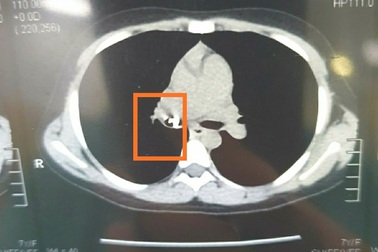

Bé gái đau ngực suốt 2 tháng sau khi được mẹ nhổ răng hàmSau khi được mẹ nhổ răng, bé gái bị ho sặc, tìm không thấy chiếc răng. Suốt 2 tháng qua, bé liên tục bị đau ngực, khó thở, tại bệnh viện bác sĩ phát hiện chiếc răng đang nằm trong phổi.